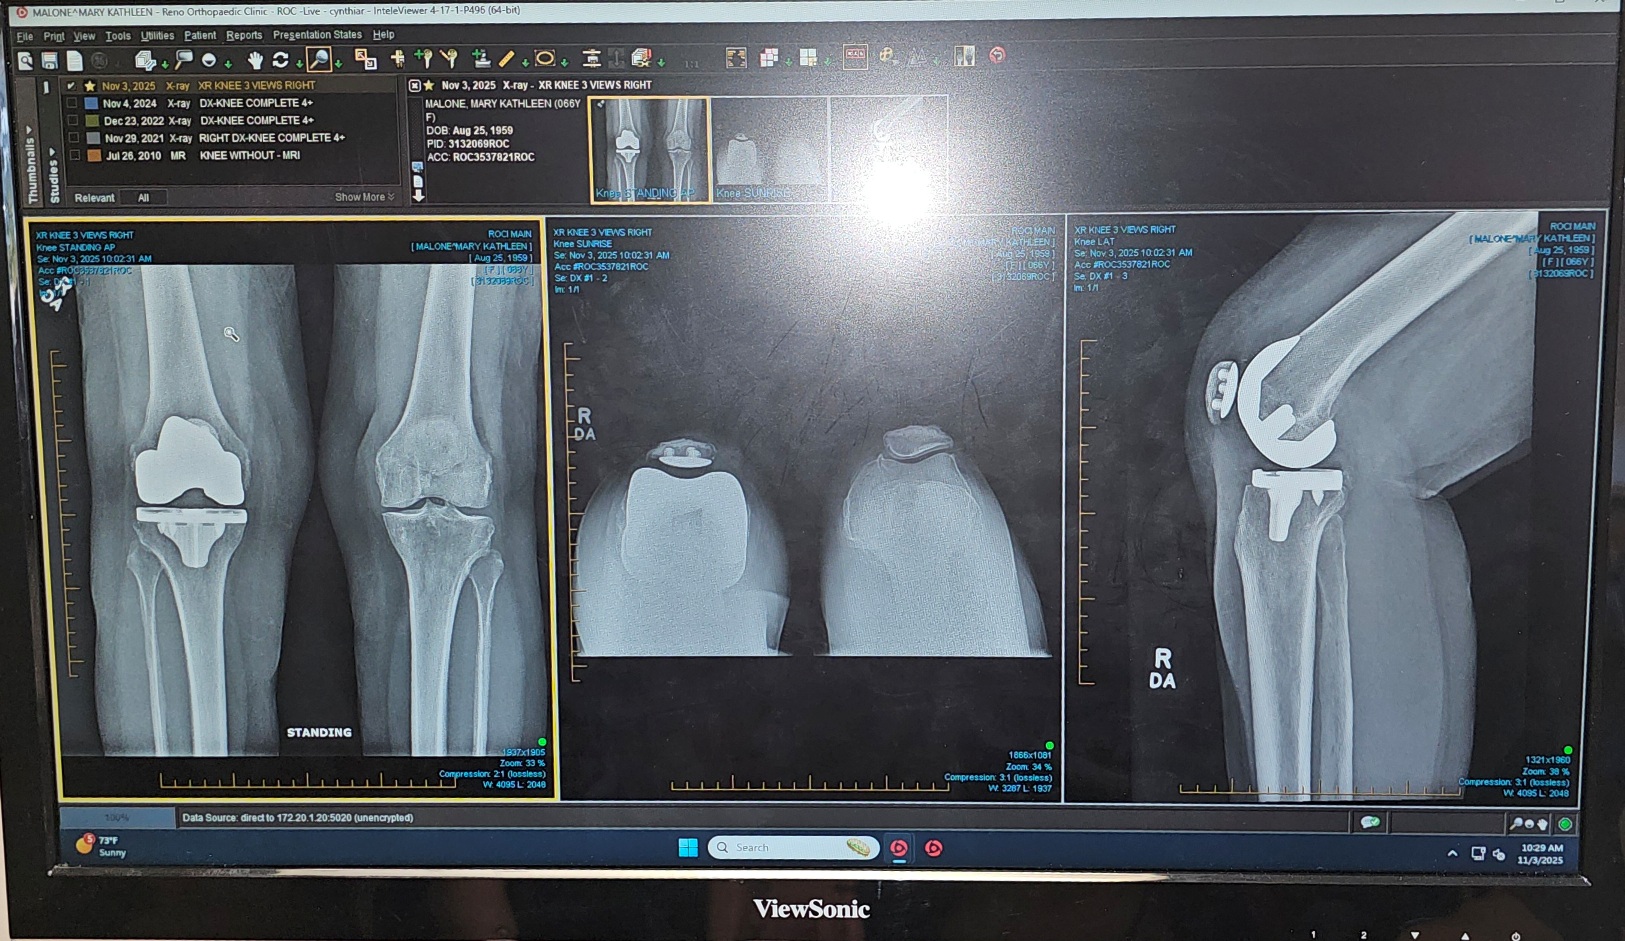

Xray shows her new knee with her other knee she still has.